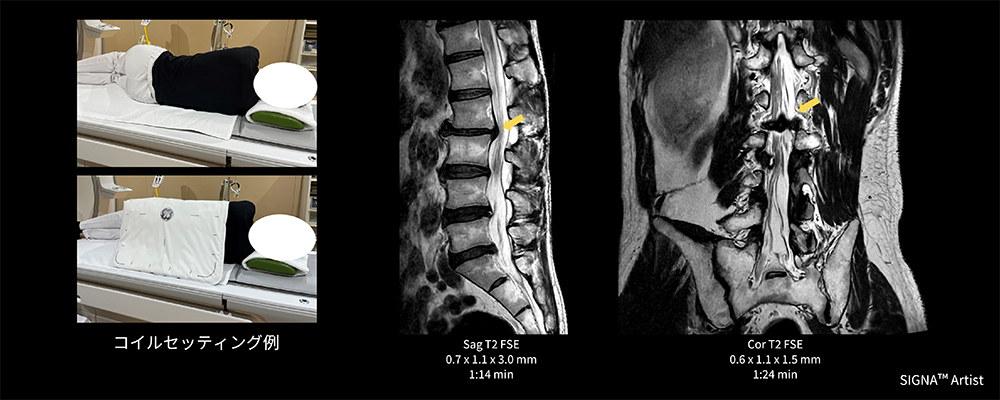

Case1 側臥位の腰椎検査

60代の男性。椎間板ヘルニアにて経過観察のため腰椎MRI検査を実施。検査当日痛みが強く、仰臥位困難なため側臥位にて検査施行(図3)。そこで、AIR™ Coilの向きを変えて使用し腰部全体にコイルをフィットさせ覆うことが出来た結果、通常の検査と遜色ない画像を取得でき、診断に貢献できた一例。

AirCoils_Shigaikadai_04.jpg図3 側臥位の腰椎検査におけるAIR™ Coilのセッティング例と臨床画像